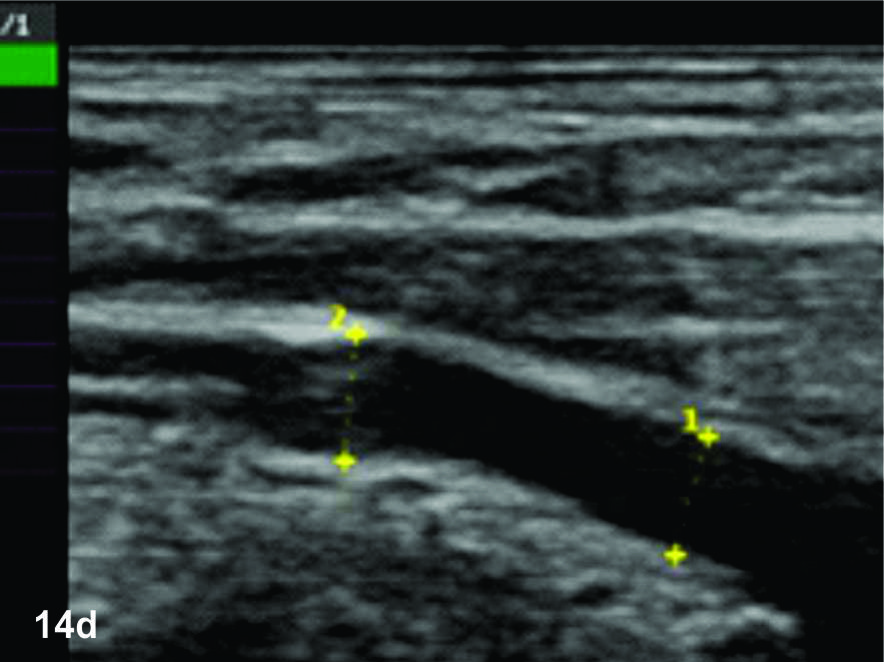

Figura 14 c y d

Lesión traumática del plexo braquial luego de accidente en moto.

C y D- cortes comparativos longitudinales sobre el tronco medio del plexo braquial (C- izquierdo sano y D- derecho patológico), se demuestra la asimetría de la raíz media del plexo, la cual se demuestra en un corte longitudinal comparativo (señalada entre calipers amarillos). La flecha blanca en D señala un fragmento óseo desplazado debido a una fractura del proceso transverso vertebral que generaba conflicto con la raíz.